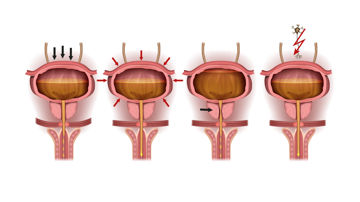

Die Blase ist ein muskulöses Hohlorgan im Becken, knapp über und hinter dem Schambein. Die Blase hat zwei Hauptfunktionen: die Speicherung und Entleerung des Urins.

Erkrankungen, Altern oder Verletzungen können zu einem Verlust der Blasenkontrolle führen, indem sie die Fähigkeit der Blase beeinträchtigen, Urin zu speichern und zu entleeren.

Als Überlaufinkontinenz wird der unfreiwillige Harnverlust bezeichnet, welcher auftreten kann, wenn die Blase aufgrund einer Blasenauslassobstruktion oder einer Unterfunktion des Detrusormuskels nicht richtig entleert werden kann. Diese Symptome werden oft als Symptome des unteren Harntraktes (LUTS, Lower Urinary Tract Symptoms) beschrieben.

Harnverhalt ist die Unfähigkeit, die Harnblase zu entleeren, wodurch eine Urinmenge zurückbleibt. Das kann zu Komplikationen führen. Wichtig ist zu wissen, dass auch dann ein Harnverhalt vorliegt, wenn die Blase zwar grundsätzlich noch entleert werden kann, aber eine zu hohe Restmenge in der Blase verbleibt.